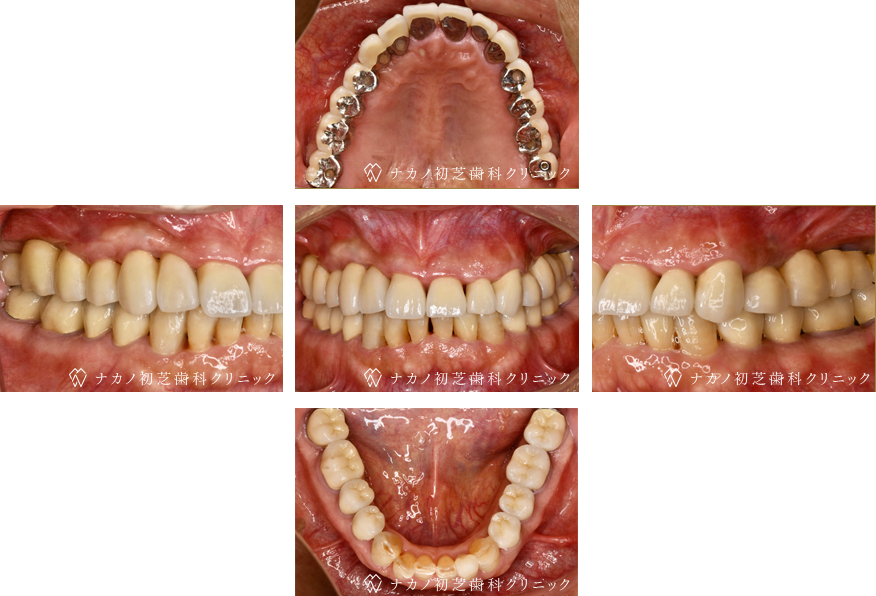

インプラント・13本 (60代女性)

BEFORE

AFTER

年齢 60代女性

治療内容 インプラント治療13本(骨造成の併用)

インプラント治療とは、歯を抜いた所にチタン製の人工歯根を埋入し、その上に歯を入れる方法です。骨を増やすことで、より審美的に治療が出来ました。費用 1本 400,000円(税込 440,000円)

リスク・副作用

腫れ・疼痛・違和感を感じるなどの症状を生じることがあります。